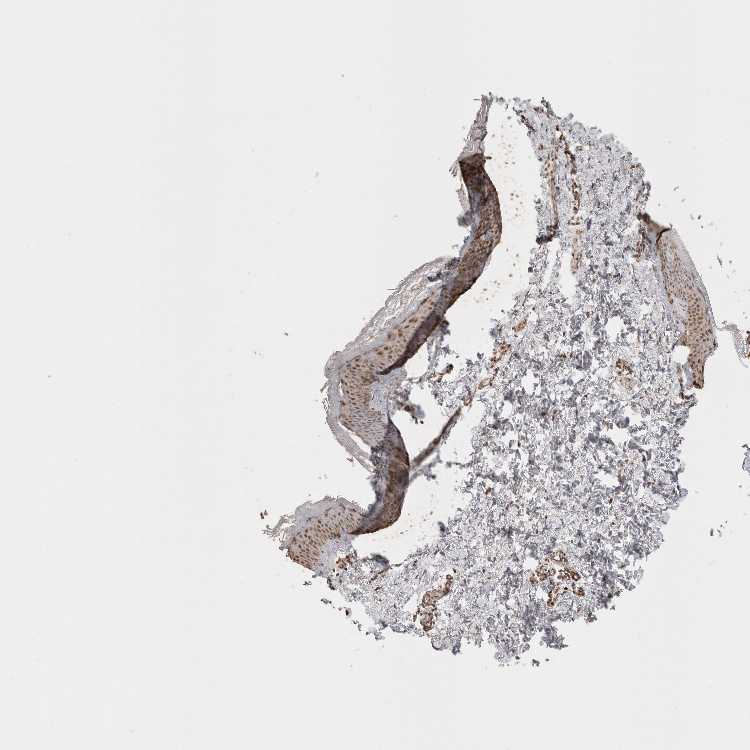

SKIN 1 - Antibody stainingi

Antibody staining in the annotated cell types in the current human tissue is reported as not detected, low, medium, or high, based on conventional immunohistochemistry profiling in selected tissues. This score is based on the combination of the staining intensity and fraction of stained cells.

Each image is clickable and will lead to virtual microscopy that enables deeper exploration of all samples and also displays staining intensity scores, fraction scores and subcellular localization as well as patient and tissue information for each sample.

Antibody HPA015652Antibody CAB025371

Langerhans Medium-

Cells in basal layer -Low

Cells in corneal layer -Not detected

Cells in granular layer -High

Cells in spinous layer -Medium

Endothelial cells -Low

Extracellular matrix -Not detected

Fibroblasts Low-

Fibrohistiocytic cells -Not detected

Keratinocytes Medium-

Langerhans cells -Medium

Lymphocytes -Medium

Melanocytes MediumLow

Vascular mural cells -Not detected